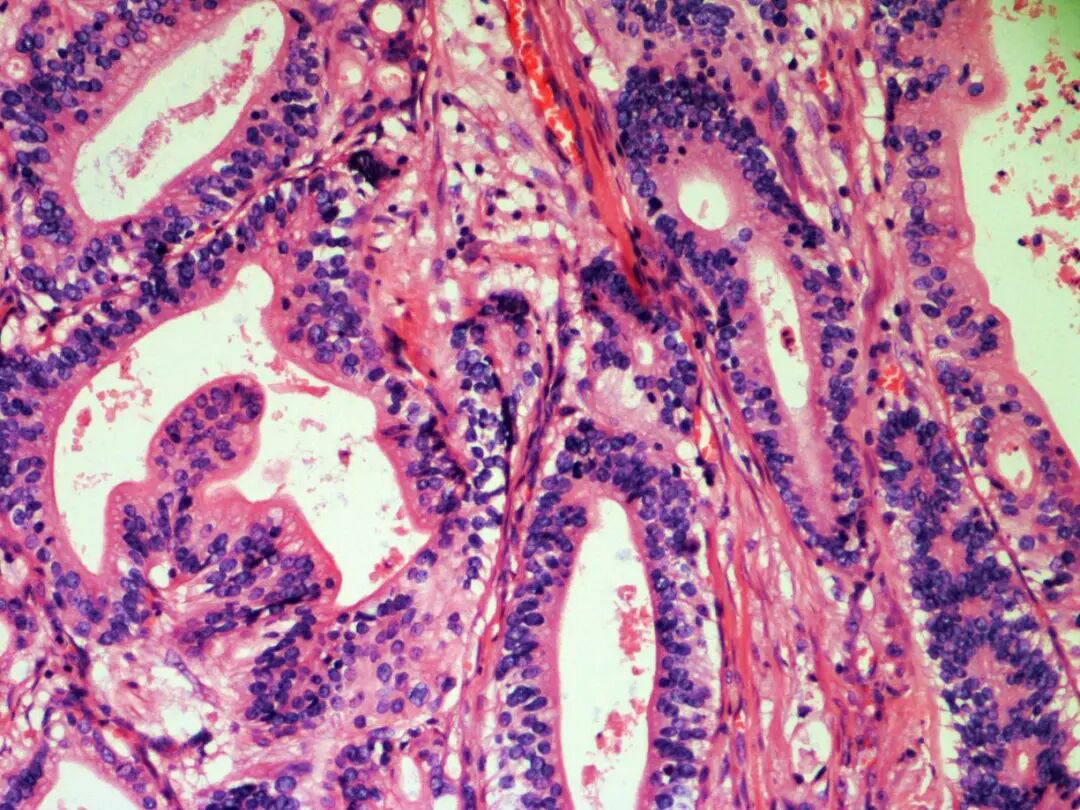

在了解斯坦氏染色之前我们先来简单了解一下HE染色,即苏木精(Hematoxylin)和伊红(Eosin)的英文首字母命名的染色。苏木精可以把细胞核染成蓝紫色,而伊红将细胞质染成红色,蓝色和红色形成了鲜明的对比,可以清晰地显示组织和细胞的形态结构(图1),它是一种快速、经济且易于掌握的方法,但它不能回答病因学、组织发生及发病机制等方面的许多问题。鉴于此,人们一直寻找其它方法探讨上述问题,并将这种在特殊情况下使用的染色技术称之为特殊染色,简称特染。换言之,特殊染色是用于显示标本中一些特殊的组织结构(成分)或细胞的染色,有利于在光镜下与其它组织或细胞区分,更好地了解观察对象的分布特点、数量变化以及达到鉴别和研究的作用。我们这里提到的斯坦氏染色就是其中的一种特殊染色方法。斯坦氏染色液是一种基于银离子的试剂盒,用于多种微生物组织的诊断,例如幽门螺旋杆菌、螺旋菌或者嗜肺军团病杆菌等。

图1_胃贲门活检组织 HE染色(20X)

所谓HE染色法就是组织切片经常规HE染色后直接在镜下观察有无HP,HP染色后菌体和背景均呈蓝紫色,主要分布于胃小凹中或胃黏膜表面的腺腔内,呈弯曲的逗点状或小点状,需要在高倍镜下仔细观察,有时与染色过程中的杂质及污染难以区别,能检测到的菌体数较少,检测的视野也较为模糊(图2)。

图2_胃镜活检贲门组织HE染色,菌体和背景均呈蓝色(40X)